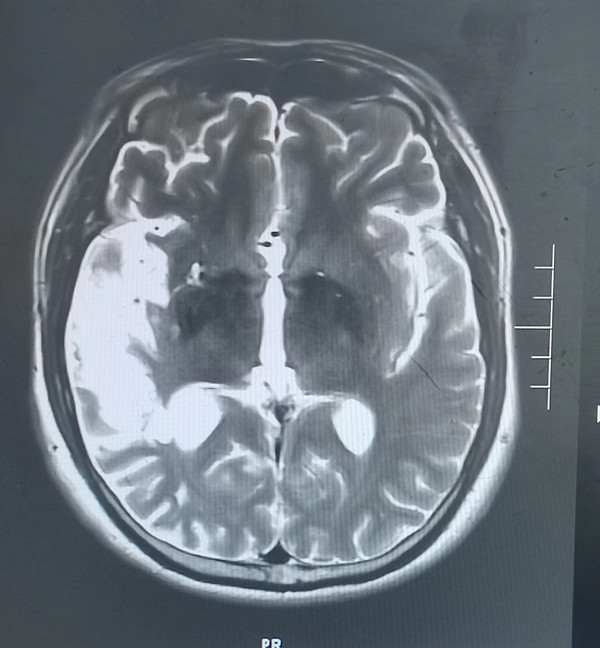

5月前46歲的徐先生因患腦梗死在西安某醫院就診,經治療后好轉,近1周再次出現腦梗死癥狀來我院就診,腦梗死導致他視野缺損,左上肢肢體無力,入院后檢查頭顱磁共振檢查發現右側顳葉大面積腦梗死,由于錯過溶栓機會,目前只能保守治療,徐先生一家郁悶至極,平時無高血壓、無糖尿病、高血脂等疾病,他按時服用藥物治療,他只是偶爾吸煙,為何反復出現腦梗死?

入院后經追問病史患者在37歲時還患有急性心肌梗死病史,當時急診溶栓后病情好轉。為明確患者反復出現腦梗死、心肌梗死原因,入院后神經內科張醫生為患者做了TCD發泡試驗,發現有明顯異常,經食道超聲檢查發現患者心臟有先天性房間隔缺損。為明確患者心梗原因,我們先行冠狀動脈造影并未發現有嚴重冠脈狹窄病變,經我院吳棟梁院長及崔旭輝主任介入團隊再次評估后考慮患者屬于典型的房間隔缺損出現反常栓塞病案。